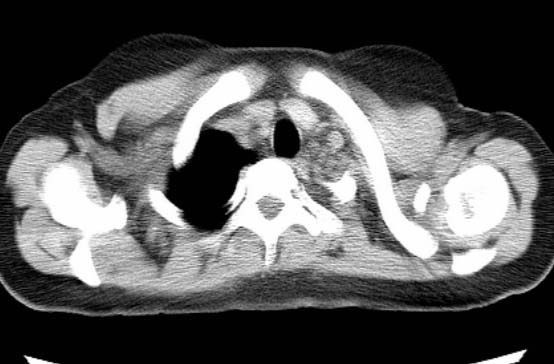

标题: CT25648:求教:是肺发育不全还是结核?

女  20岁。一月前咳血,诊“肺结核”抗痨治疗一月后,咳血停止,现复查。病人精神好。前后ct片对比未见明显变化。既往体检“正常”

1)考虑左肺结核并肺不张、支气管扩张。2)纵隔疝。

考虑左肺结核,左肺毁损,纵膈左偏,既往体检正常不可靠,tb一个月也不会这个样子的,有钙化,应该病程较长,冰冻三尺非一日之寒!